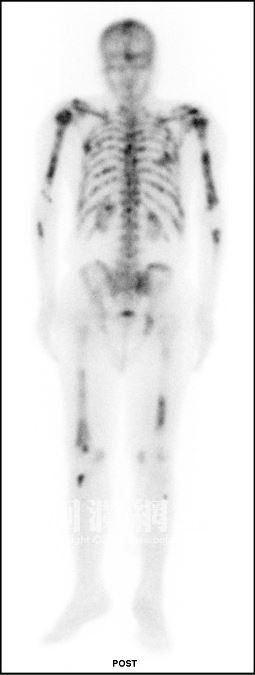

75歲黃先生,3年前發現罹患第四期攝護腺癌且合併骨骼轉移,雖然積極配合醫師的治療甚至也使用了賀爾蒙療法,卻仍飽受疼痛之苦,止痛藥不再止痛,黃先生幾乎終日臥床,面無表情也沉默不語,令家人相當心疼。所幸今年3月衛福部將「鐳223同位素」納為全民健保給付項目,門諾醫院核子醫學科便立即申請「鐳223同位素」替黃先生施打治療,預計共6次的施打療程,至今已施打至第2劑,不僅大幅改善疼痛,也提升了生活品質,黃先生說,雖然不知道「鐳223」能夠延長自己多久的生命,但至少在生命最後的這段路,可以活得更舒服、快樂就已感到滿足!

游冬齡說,鐳223同位素經靜脈注射,藥物抵達骨頭後就能殺死骨轉移的癌細胞,降低疼痛且減少對其他正常組織的傷害。不僅施打完後就可返家,也不需擔心輻射更不用隔離,能夠正常生活。療程為每4週注射藥物,共需進行6劑注射,不僅能有效減緩疼痛,最重要的是提升生活品質、增加自信心,才能勇敢面對病魔挑戰,延長生命。